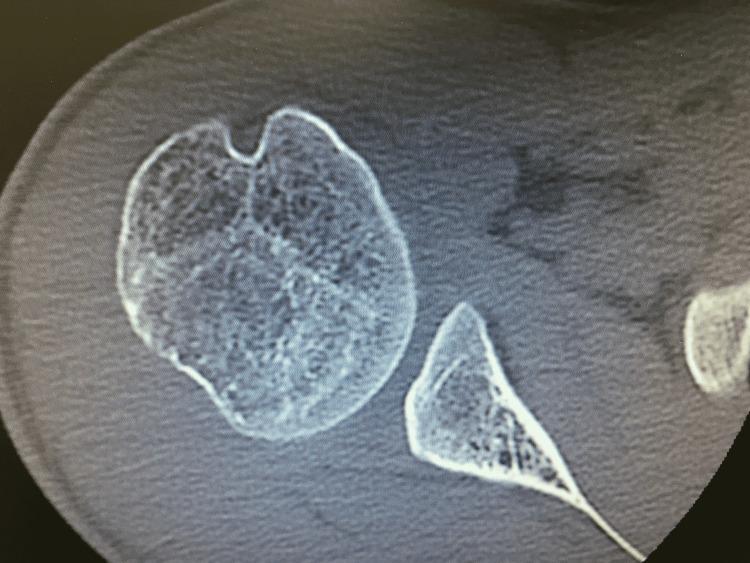

复杂的肩肱关节后向不稳病例管理

Complex Posterior Glenohumeral Instability Case Management.

A 21-year-old male patient suffering from insidious shoulder instability from neurogenic and structural attenuation of shoulder stabilizer, due to old minor cerebrovascular accident, presented with a two-year history of repetitive shoulder dislocation, operated by fixing the biceps tendon to its insertion on the superior labrum, correction of the glenoid version and reattaching the subscapular tendon along with a new technique for stabilization of the shoulder replicating the coracohumeral ligament with a ligament advanced reinforcement system (LARS) transplant. Following structured physical therapy, our patient returned to normal daily activities at 15 months.

摘要

一名21岁男性患者,因陈旧性轻度脑血管意外导致肩部稳定器神经源性和结构性减弱,出现隐匿性肩部不稳定,有两年反复肩关节脱位病史。手术方式为将肱二头肌肌腱固定于其在上盂唇的附着点,矫正肩胛盂形态,并重新附着肩胛下肌腱,同时采用一种新的肩部稳定技术,即使用韧带推进增强系统(LARS)移植来复制喙肱韧带。经过系统的物理治疗,该患者在15个月时恢复了正常日常活动。